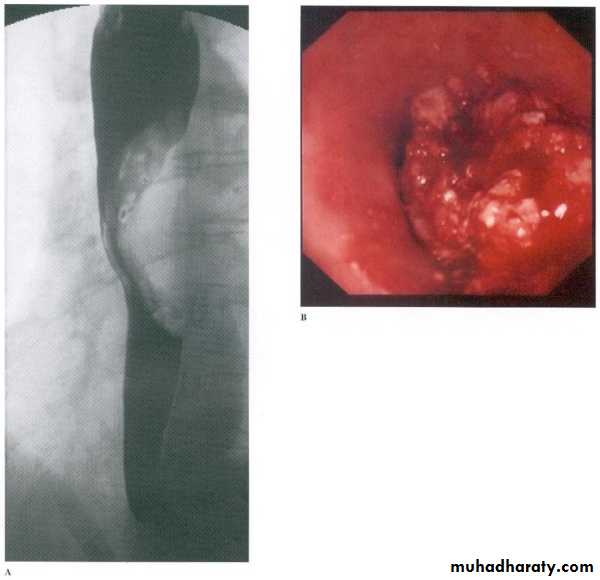

Infectious esophagitis

Candida esophagitis in patient with an infectious esophagitis due to candida , the barium shows numerous fine erosions & plaques causing shaggy outline of the osophagus due to Candida albicans in immunocompromised patient.middle year old female with a past medical history significant for HIV/AIDS comes in with complaint of loosing their weight over the past 2 weeks with pain & difficulty on swallowing …. Also feels like food is getting stuck in her throat

What is your diagnosis ??????????